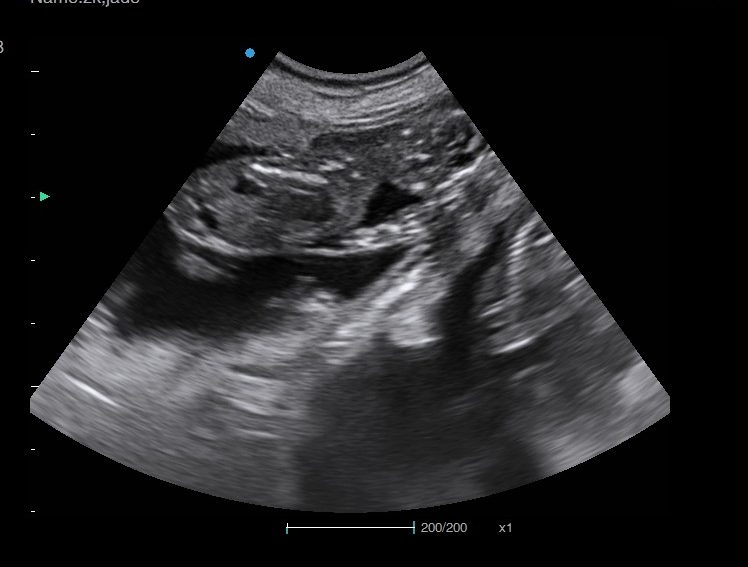

Ultrasound pregnancy scanning is a safe, non-invasive way to confirm pregnancy in dogs and cats, offering breeders and pet owners peace of mind and vital information to support responsible care. It allows us to detect gestational sacs, assess foetal development, and estimate litter size—all while ensuring the wellbeing of the animal.

Pregnancy can sometimes be detected as early as Day 18 post-mating, but scanning at this stage is not routinely recommended. Embryos are still developing and may not be clearly visible, and there is a natural risk of embryo resorption, which can lead to misleading or inconclusive results.

For the most accurate and reliable scan, we advise booking between Day 25 and Day 32, when pregnancy is more easily confirmed and foetal structures are clearer. If an early scan is performed and no pregnancy is detected, we offer a FREE complimentary re-scan after 7 days at the clinic to ensure clarity and support informed decision-making.

Our approach balances early insight with ethical care—always prioritizing the comfort of the animal and the accuracy of the results.

Gallery